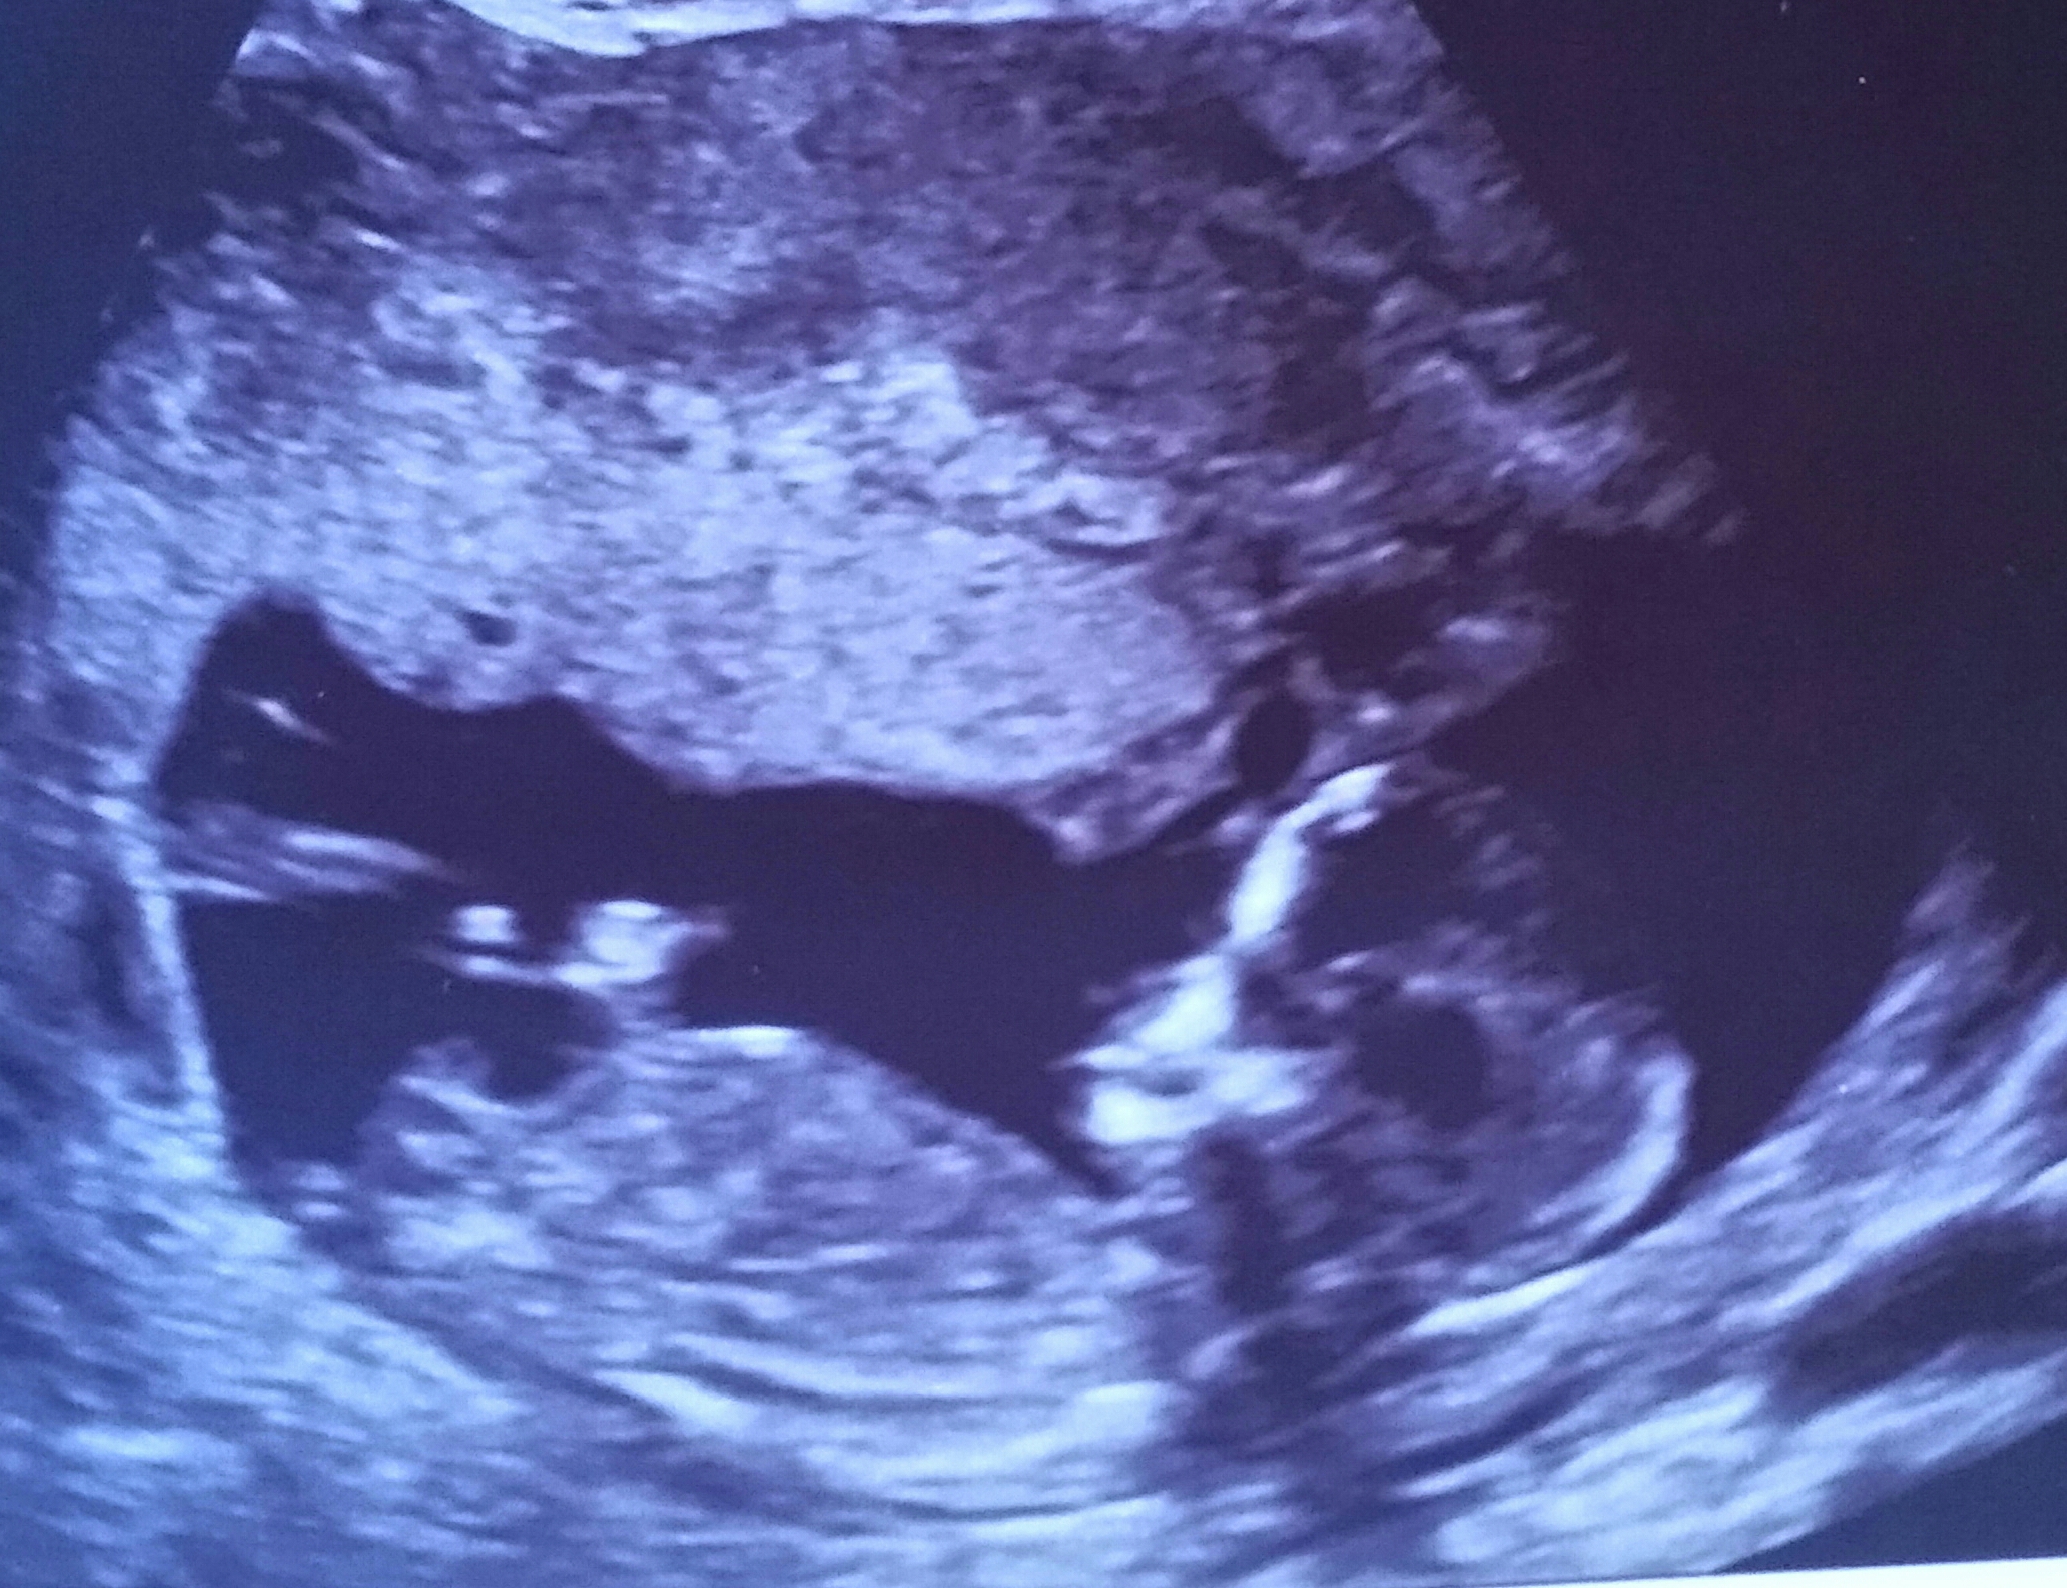

Tentative boy lean.

Do you see stacking?

Boy guess from me. The nub looks short and stacked on the end.

It's a girl. Confirmed at 21 weeks.

Just had a scan at 21 weeks and it's actually a girl.